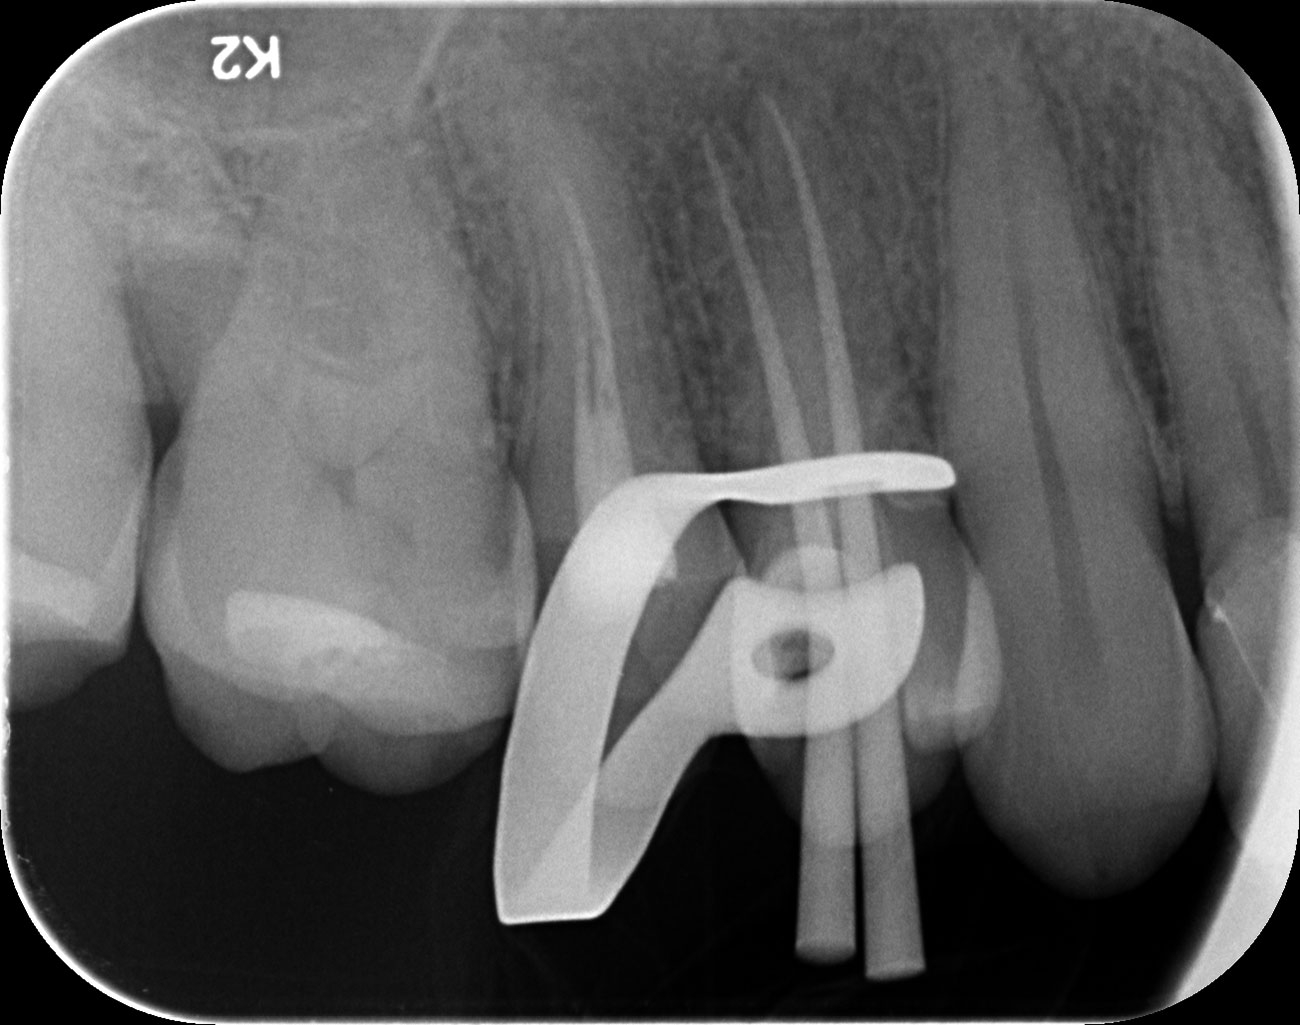

Dantų kanalų gydymas